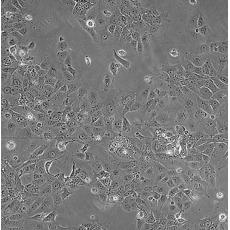

HCC827

中文名稱 人非小細(xì)胞肺癌細(xì)胞

組織來源 肺腺癌;女性

生長特性 adherent

形態(tài)特征 epithelial

細(xì)胞描述 This lung adenocarcinoma has an acquired mutation in the EGFR tyrosine kinase domain(E746-A750 deletion).